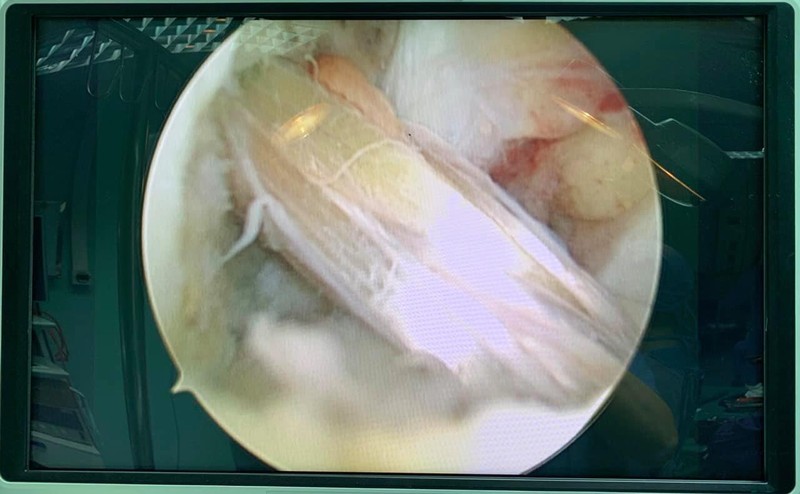

Dây chằng chéo trước ccủa bệnh nhân sau khi được tái tạo thành công. Ảnh: BVCC

Hiện, Khoa Ngoại Thần Kinh - Chấn thương Chỉnh hình Bệnh viện Hữu Nghị đã triển khai phẫu thuật nội soi tái tạo dây chằng chéo trước bằng phương pháp All Inside. Đây là phương pháp tiên tiến nhất hiện nay trong điều trị bệnh lý này. Phương pháp này có ưu điểm: mảnh ghép dây chằng lớn hơn, tiết kiệm nguồn gân ghép, cố định mảnh ghép dây chằng vững chắc hơn giúp bệnh nhân có thể quay trở lại các hoạt động thể thao một cách sớm nhất.